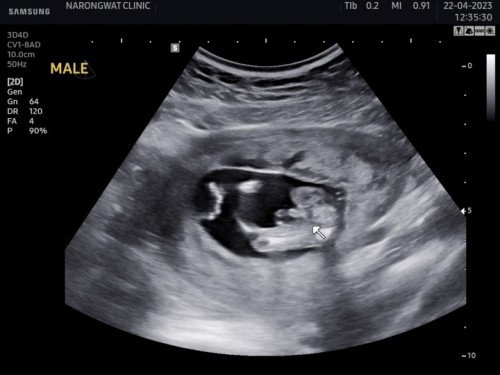

ซาวด์เพศลูก 14w+2 แบบนี้ชัดหรือยังคะ อยากเริ่มซื้อของเตรียมให้น้องแล้วค่ะ🥰

ชัดเลยค่าแม่ ด้านบนซ้ายมีคำว่า MALE ได้น้องผู้ชายคับ ดีใจด้วยนะคะ

ตอนแรกก็ไม่มั่นใจค่ะ คิดว่า14wน่าจะเร็วไป แต่หมอบอกเห็นจู๋ กลัวน้องจะหลอกแม่

ชัดเลยค่ะเเม่โผล่ชัดมาก บ้านนี้ก็ผช.เหมือนกันจ้ารู้ตอน14w.